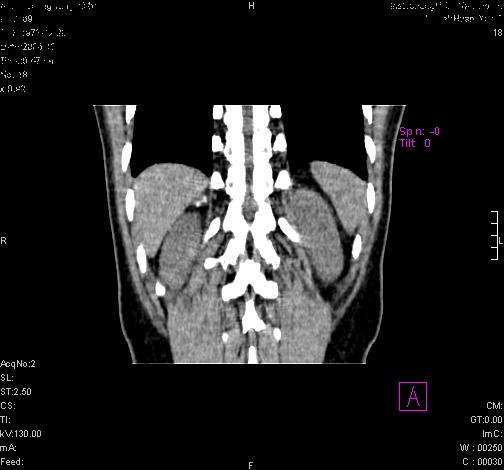

标题: CL0340:【】肾上腺囊肿,比较典型。

患者为年轻女性,查体发现右侧肾上腺囊性占位。无临床体征。

这么漂亮的图像,一看一目了然。典型的右侧肾上腺囊肿,周围有钙化。感谢搂主!

“肾上腺囊肿组织学分为4类:1)内皮细胞性,2)假性囊肿,3)寄生虫性,4)上皮细胞性。其中内皮细胞性最为常见。假性囊肿多为肾上腺内出血后遗留囊腔,囊壁无上皮细胞。寄生虫性多为包虫病引起。上皮性则很少见。”

这么明显的弧形钙化,多考虑包虫病所致的寄生虫性囊肿。

这么漂亮的图像,一看一目了然。典型的右侧肾上腺囊肿,周围有钙化。感谢搂主

右侧肾上腺囊性密度灶囊壁有钙化。考虑肾上腺囊肿,结核?